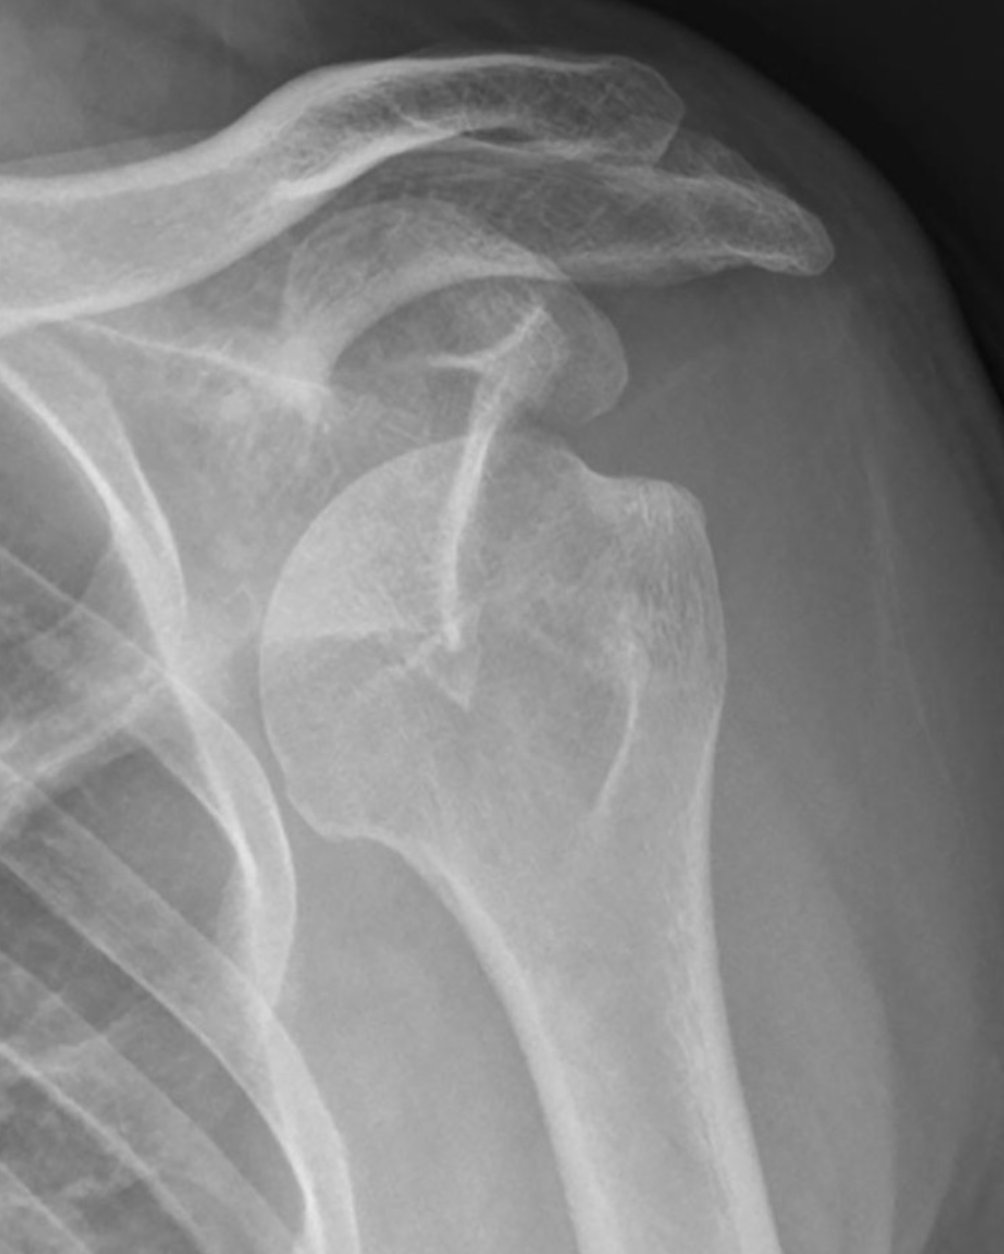

X-ray image of a shoulder joint showing the clavicle, scapula, and humerus.

A glenohumeral dislocation occurs when the head of the humerus is forced out of the shoulder socket, typically due to trauma, sports injuries, or sudden falls.

This condition causes immediate, intense pain, visible deformity, and an inability to move the arm. Because the shoulder is the most mobile joint in the body, it is also particularly vulnerable to instability and recurrent dislocations.